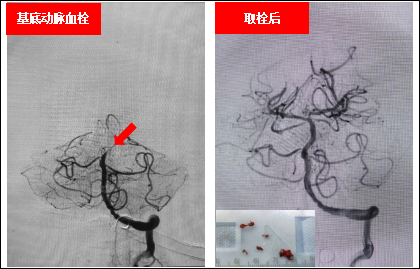

神经介入诊治优势:神经介入专业组开展缺血性及出血性神经介入手术治疗处于国内领先水平。在颅内外狭窄动脉支架成形术、慢性闭塞性脑血管病的介入再通治疗、急诊动脉取栓治疗、颅内动脉瘤的介入治疗、静脉窦狭窄及急性血栓介入治疗方面具有丰富的经验。较早的将高分辨核磁技术应用于脑血管病的诊治中,在介入手术患者的术前评定及脑卒中病因分型等方面均发挥了重要的作用。在脑卒中病因筛查、个体化抗栓治疗、青年卒中诊治及急危重症脑卒中的急救和处置方面精准施治,效果显著。

基底动脉闭塞患者接受机械取栓治疗前后对比图